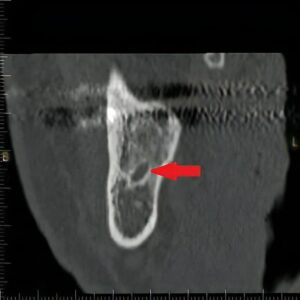

- 上顎洞穿孔

- 上あごには、「上顎洞」と呼ばれる空洞があります。時に親知らずを抜くとここに繋がってしまう方もいるぐらい、骨が薄いです。そのため上あごにインプラントを植え込む際に、ここまで穴を開けてしまう可能性があります。

このステントを装着した状態で、CT撮影を行い、どこにインプラントを入れ、どのように歯を並べられるかを調べます。同時に、撮影データを使いパソコン上で手術シミュレーションを行うことにより、手術前に上記の偶発症・合併症などの手術リスクを評価していきます。